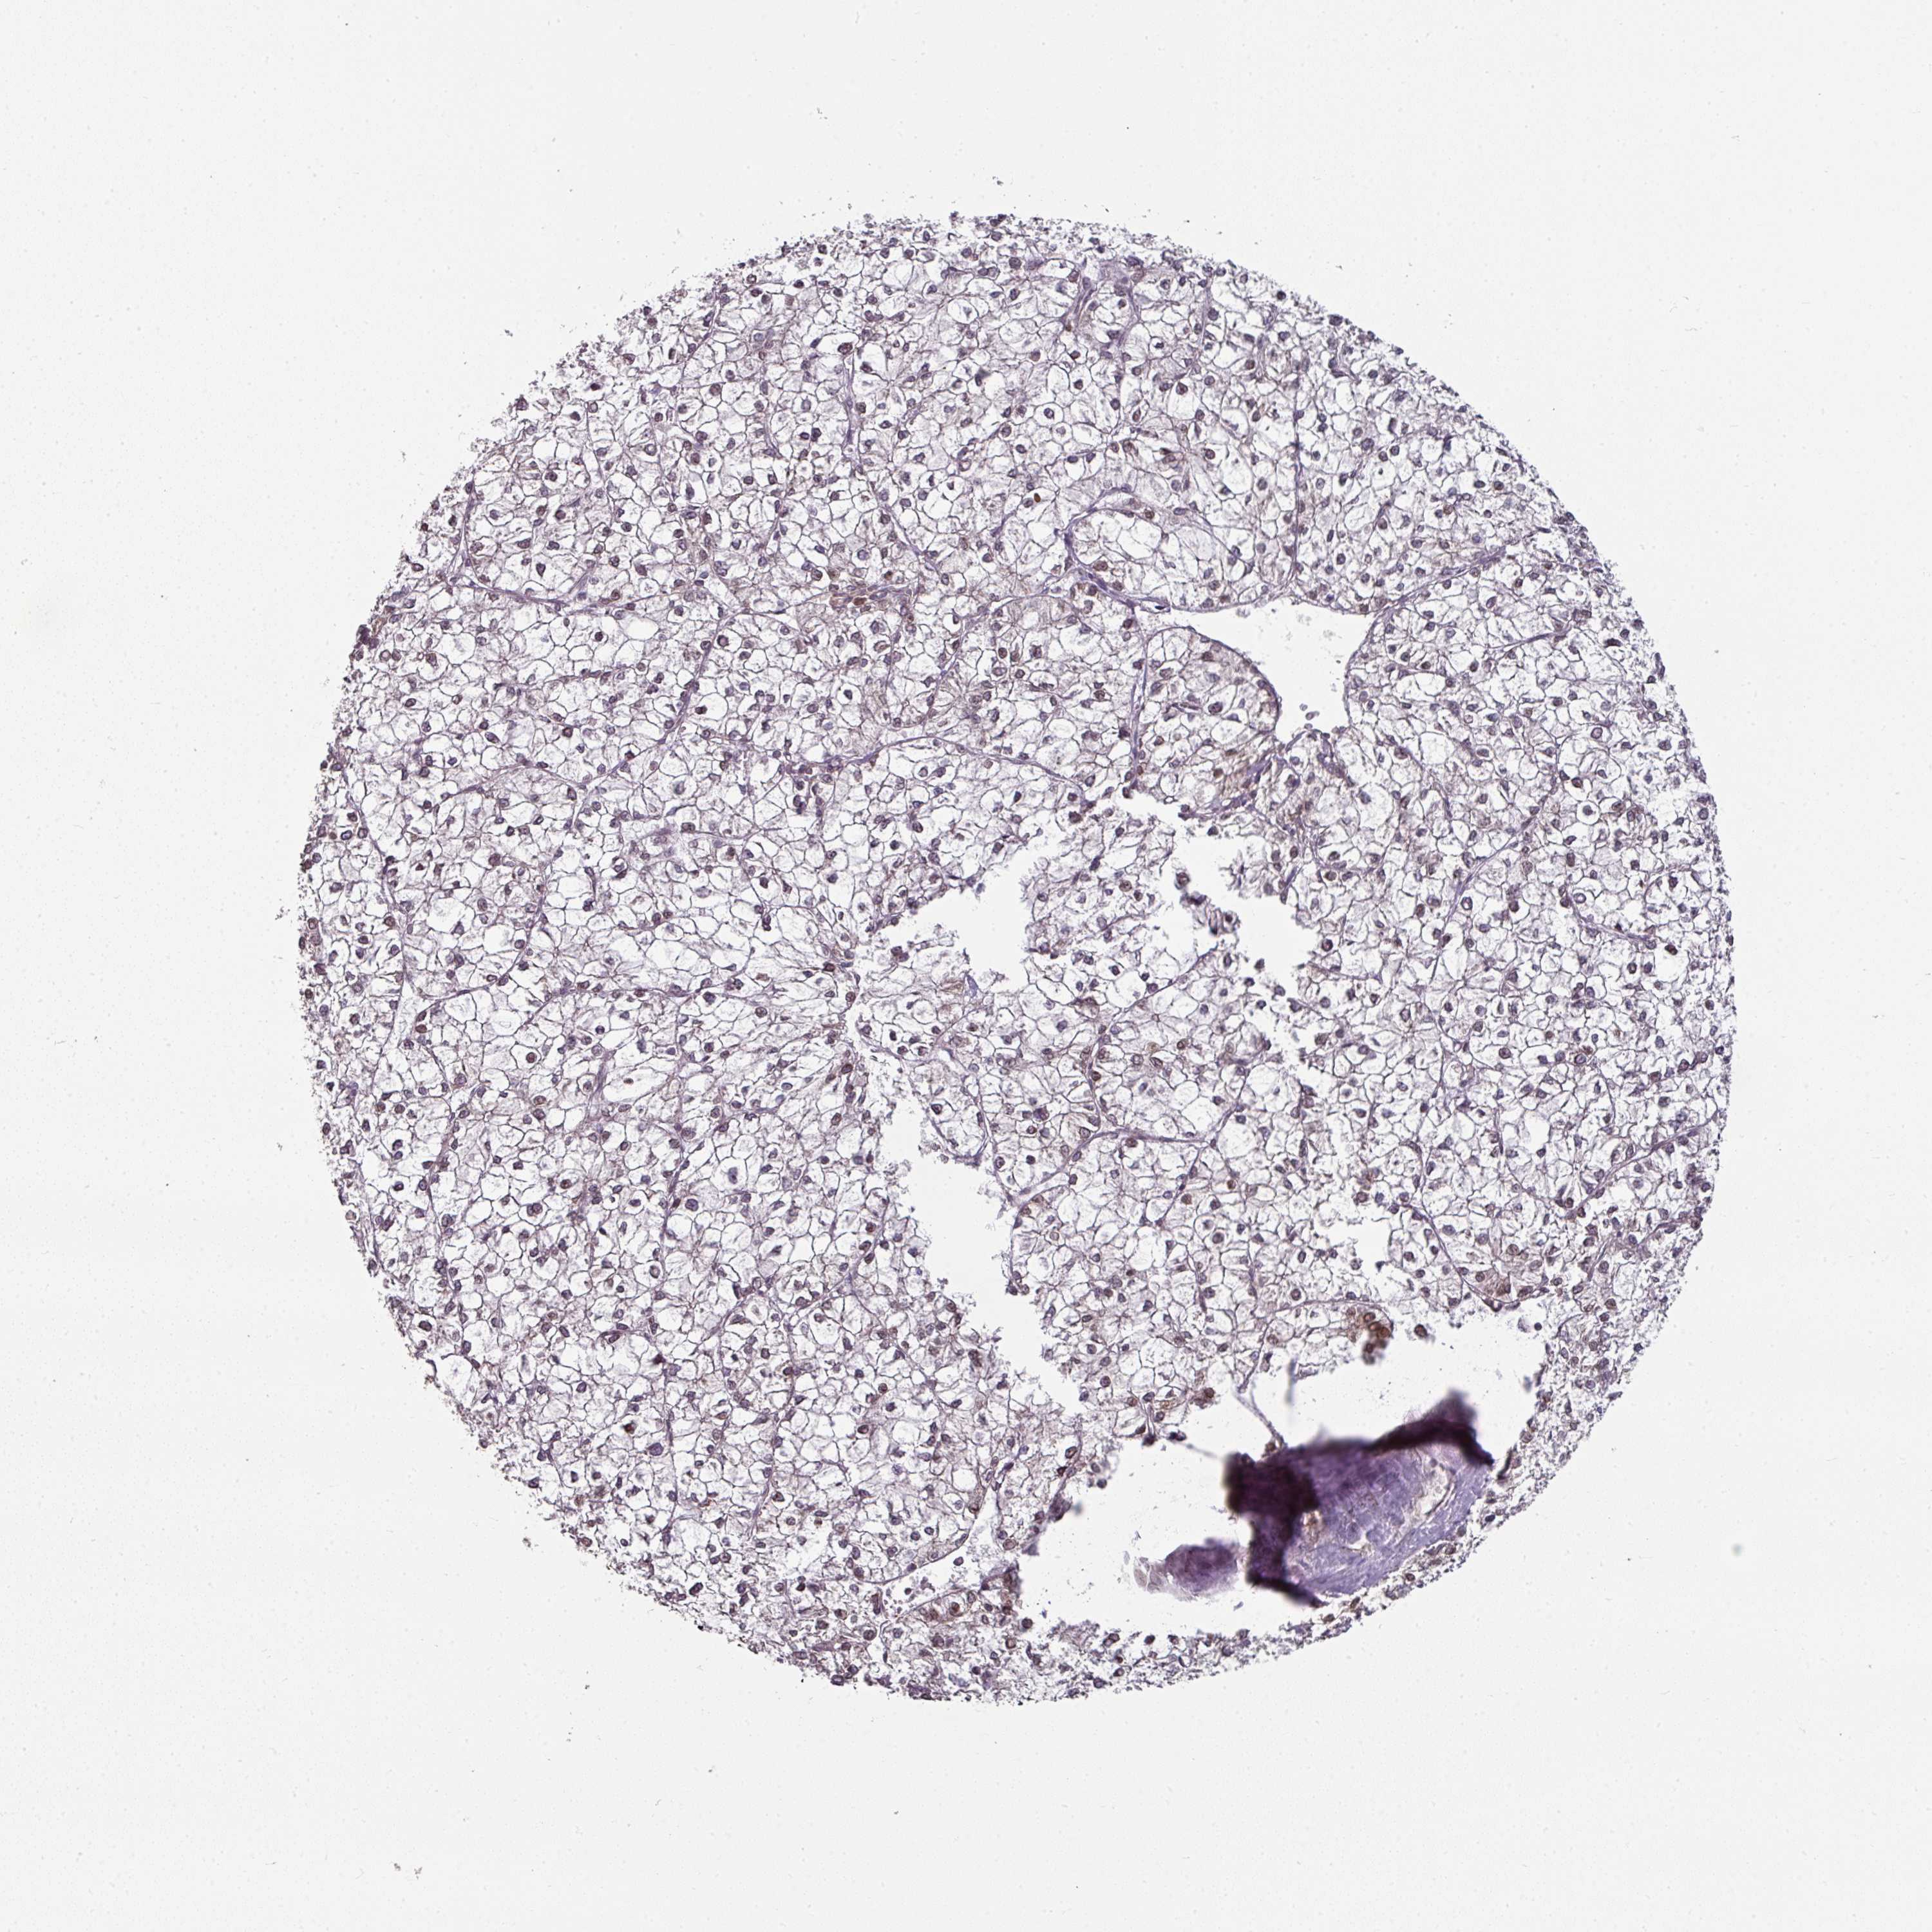

LIVER CANCER - Protein expressioni

A mouse-over function shows sample information and annotation data. Click on an image to view it in a full screen mode. Samples can be filtered based on level of antibody staining by selecting one or several of the following categories: high, medium, low and not detected. The assay and annotation is described here.

Note that samples used for immunohistochemistry by the Human Protein Atlas do not correspond to samples in the TCGA dataset.

Antibody stainingi

Antibody staining in the annotated cell types in the current human tissue is reported as not detected, low, medium, or high, based on conventional immunohistochemistry profiling in selected tissues. This score is based on the combination of the staining intensity and fraction of stained cells.

Each image is clickable and will lead to virtual microscopy that enables deeper exploration of all samples and also displays staining intensity scores, fraction scores and subcellular localization as well as patient and tissue information for each sample.

Antibody HPA050110

Antibody CAB004293

Staining

High

Medium

Low

Not detected

Intensity

Strong

Moderate

Weak

Negative

Quantity

>75%

75%-25%

<25%

None

Location

Nuclear

Cytoplasmic/membranous

Cytoplasmic/membranous,nuclear

Carcinoma, Hepatocellular, NOS

Cholangiocarcinoma